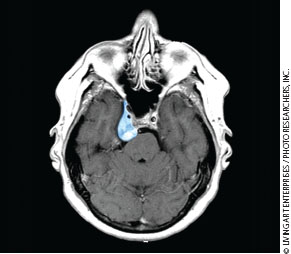

脑膜瘤约占全部颅内肿瘤的15%。它们轮廓清晰,很少转移。在局部,它们沿着阻力较小的平面扩散,如硬膜层。脑膜瘤通过长入哈弗氏管而不是骨侵蚀延伸到骨中;因此,反应性骨形成是常见的发现。脑膜瘤由致密的纤维组织组成,往往血管丰富。大多数颅底病变沿岩颞骨或蝶骨大翼颞下表面发现,偶尔在嗅沟中发现。